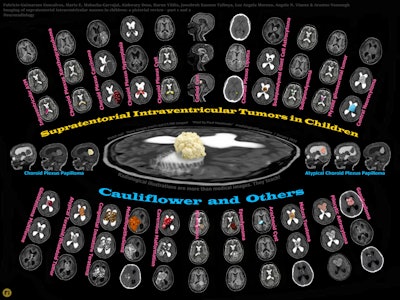

Conceptually, I think it is possible to define the term “radiological illustration” as an emerging discipline that transforms medical imaging data into an aesthetic and didactic narrative. I emphasize that with the motto “pixel by pixel handmade.” I am trying to open a “new path” for the use of visual communication in medical education by trying to combine scientific accuracy in radiological terms with artistic creativity. With this statement, I am trying to express that instead of modifying radiological images, I draw each pixel by hand using technological tools and create a new visual that is both artistically and scientifically original, while remaining faithful to radiological principles.

It’s important to note that radiological illustration should not be confused with medical illustration. The former has yet to be systematically defined in the literature. I believe it deserves recognition as a distinct sub-branch within the broader medical illustration domain.

In September 2025, I had the honor of exhibiting 35 selected illustrations at an international neuroradiology congress in Istanbul, jointly organized by the European Society of Neuroradiology, the American Society of Neuroradiology, and the Turkish Society of Neuroradiology. There were over 1,500 attendees. For the first time, my illustrations were displayed as true works of art under gallery lights and among a crowd. It was an unforgettable experience that left me with deep emotional memories.